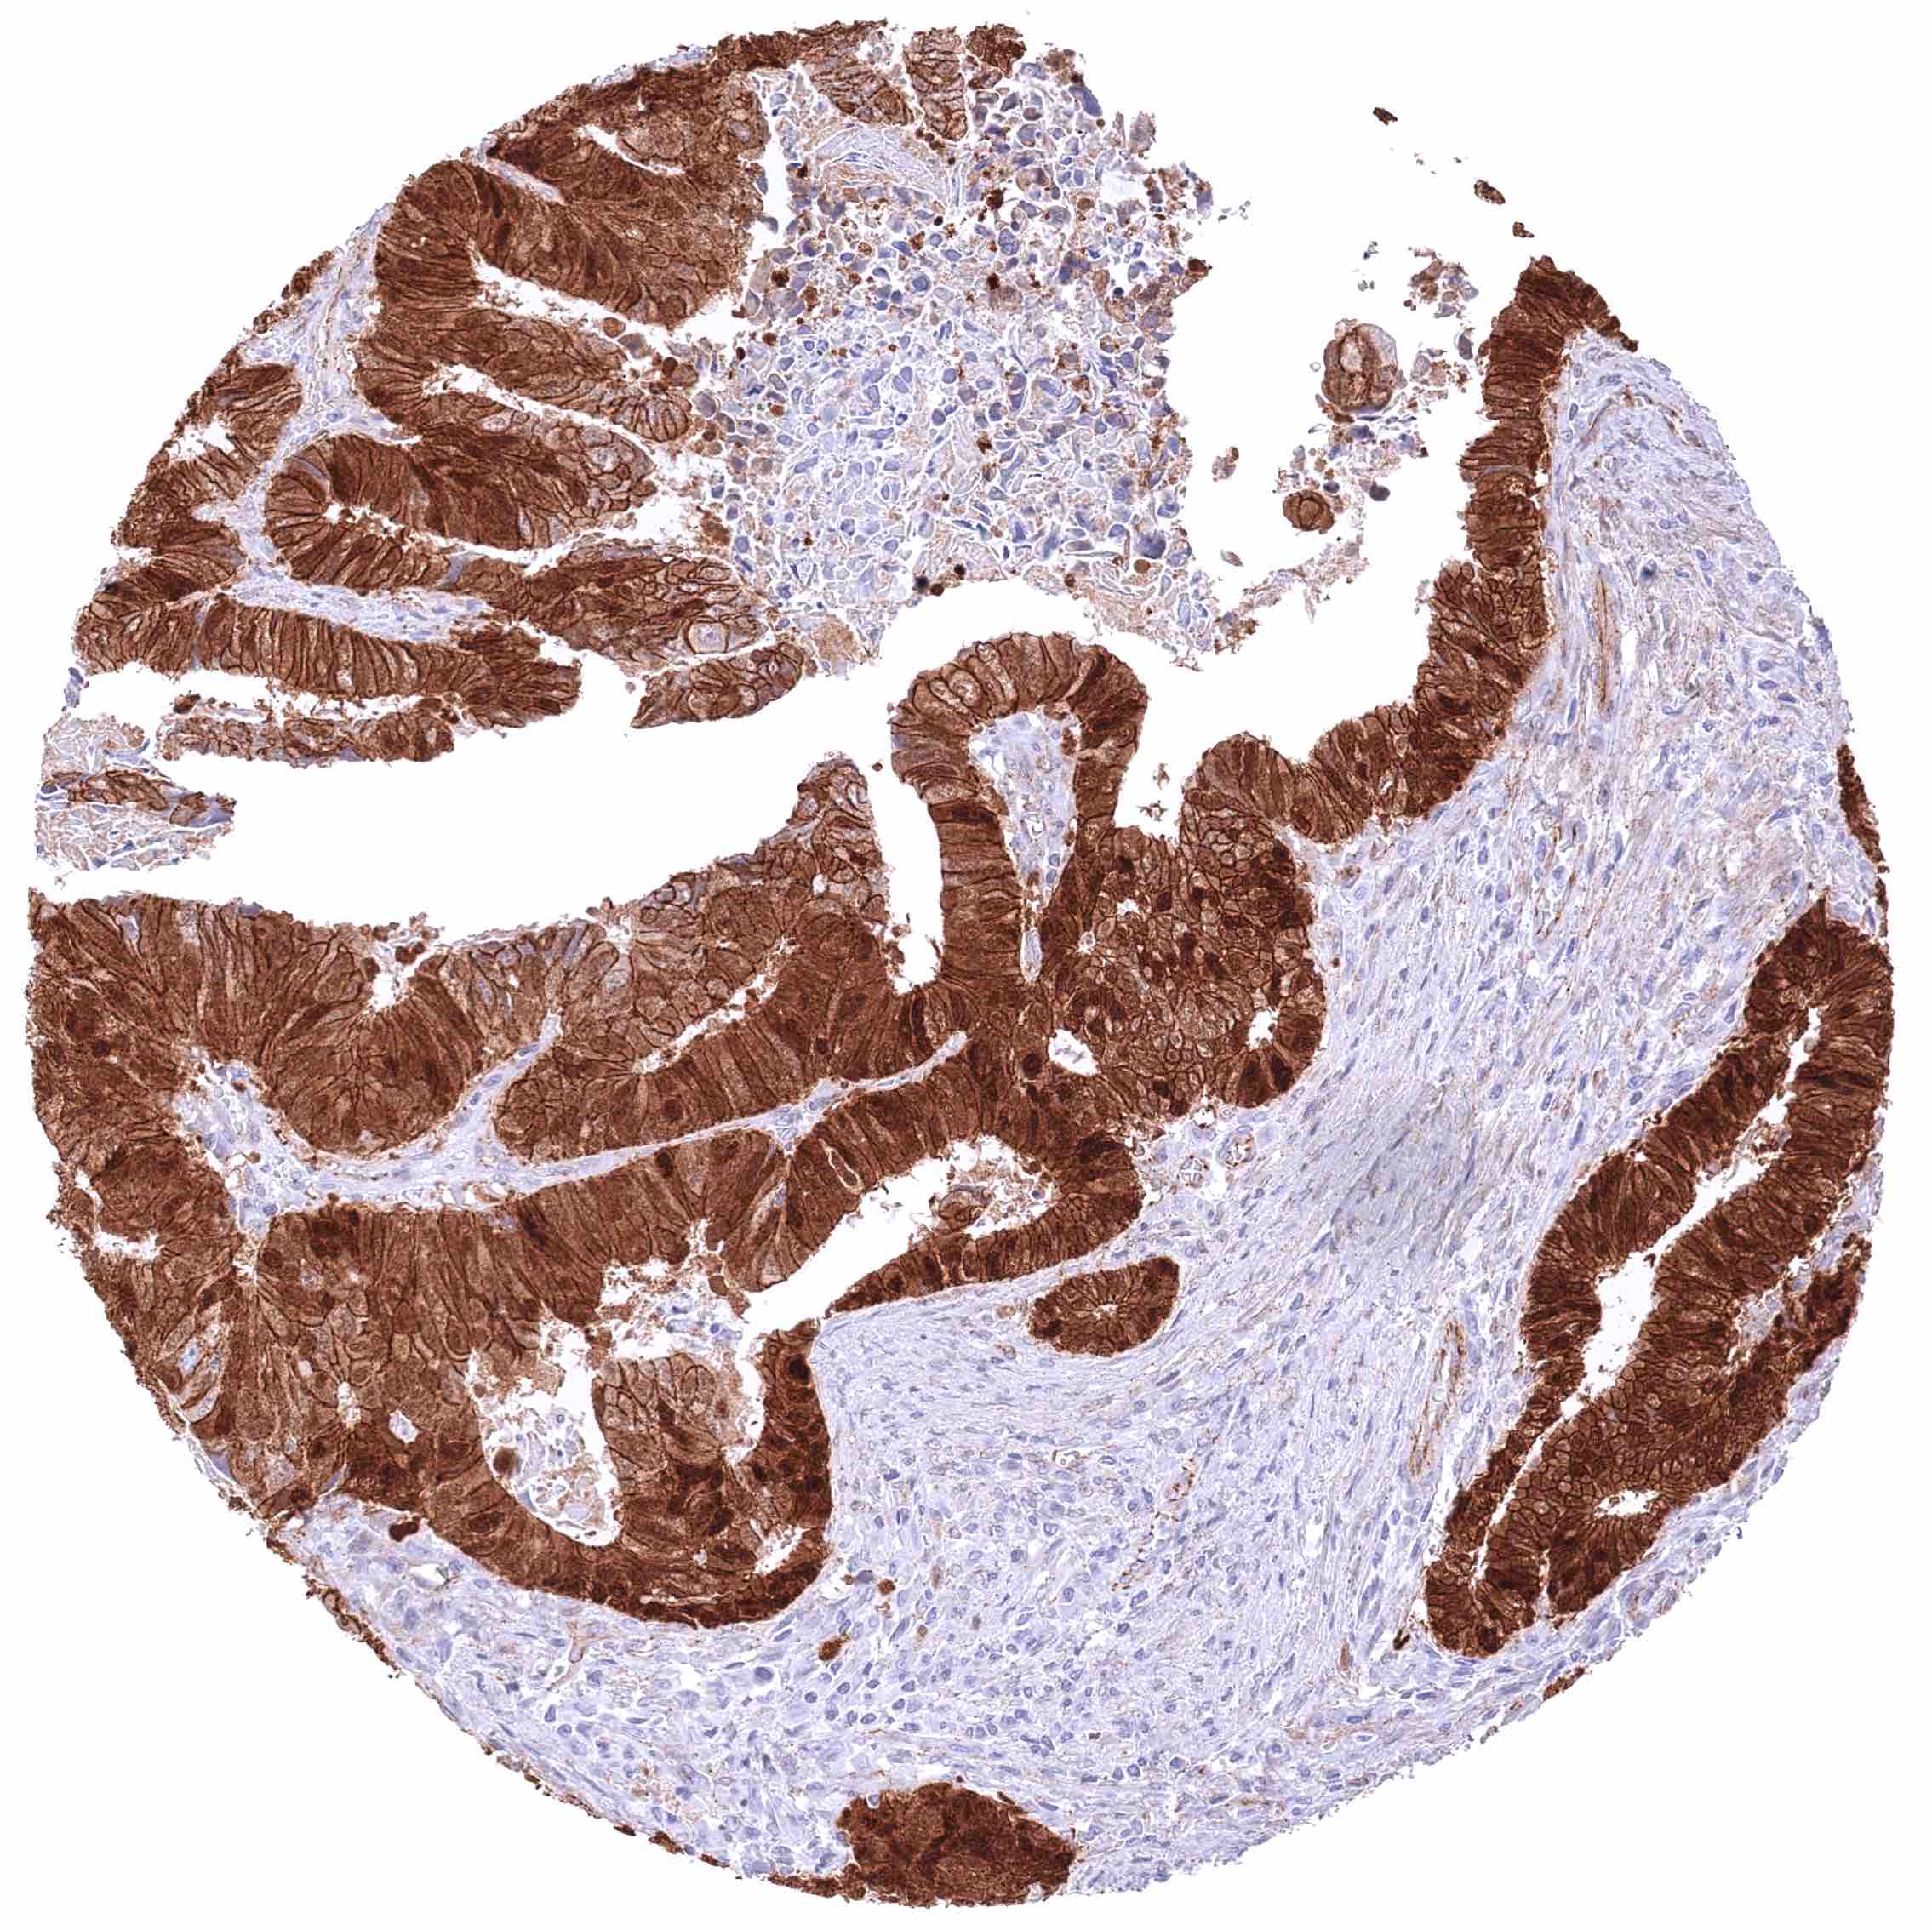

Prostate – Adenocarcinoma (Gleason 5+5=10) with strong membranous, moderate cytoplasmic, and strong nuclear β-Catenin staining of tumor cells.